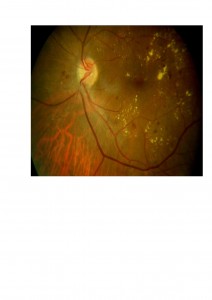

2. El tratamiento con láser puede conseguir mejorías significativas en determinados tipos de edema macular diabético (el denominado edema macular focal que se caracteriza por la abundancia de exudados lipídicos en la mácula). Os mostramos un ejemplo en el que podéis comprobar cómo desaparecen los exudados lipídicos amarillentos después de la fotocoagulación de la mácula.